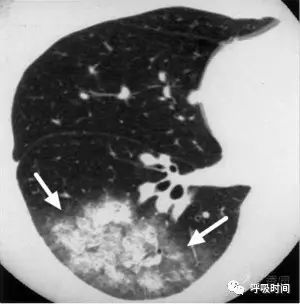

4. 空洞性病变

薄壁空洞——厚度<3 mm;厚壁空洞——厚度>3 mm;无壁空洞。

相对应的病变:肺脓肿、肺结核、肺癌、转移瘤、肉芽肿性血管炎(韦格肉芽肿)等(见图 17 ~ 图 20);无壁空洞鉴于干酪性肺结核。

图 19 肺转移瘤:双肺弥漫分布多个圆形薄壁空洞

图片